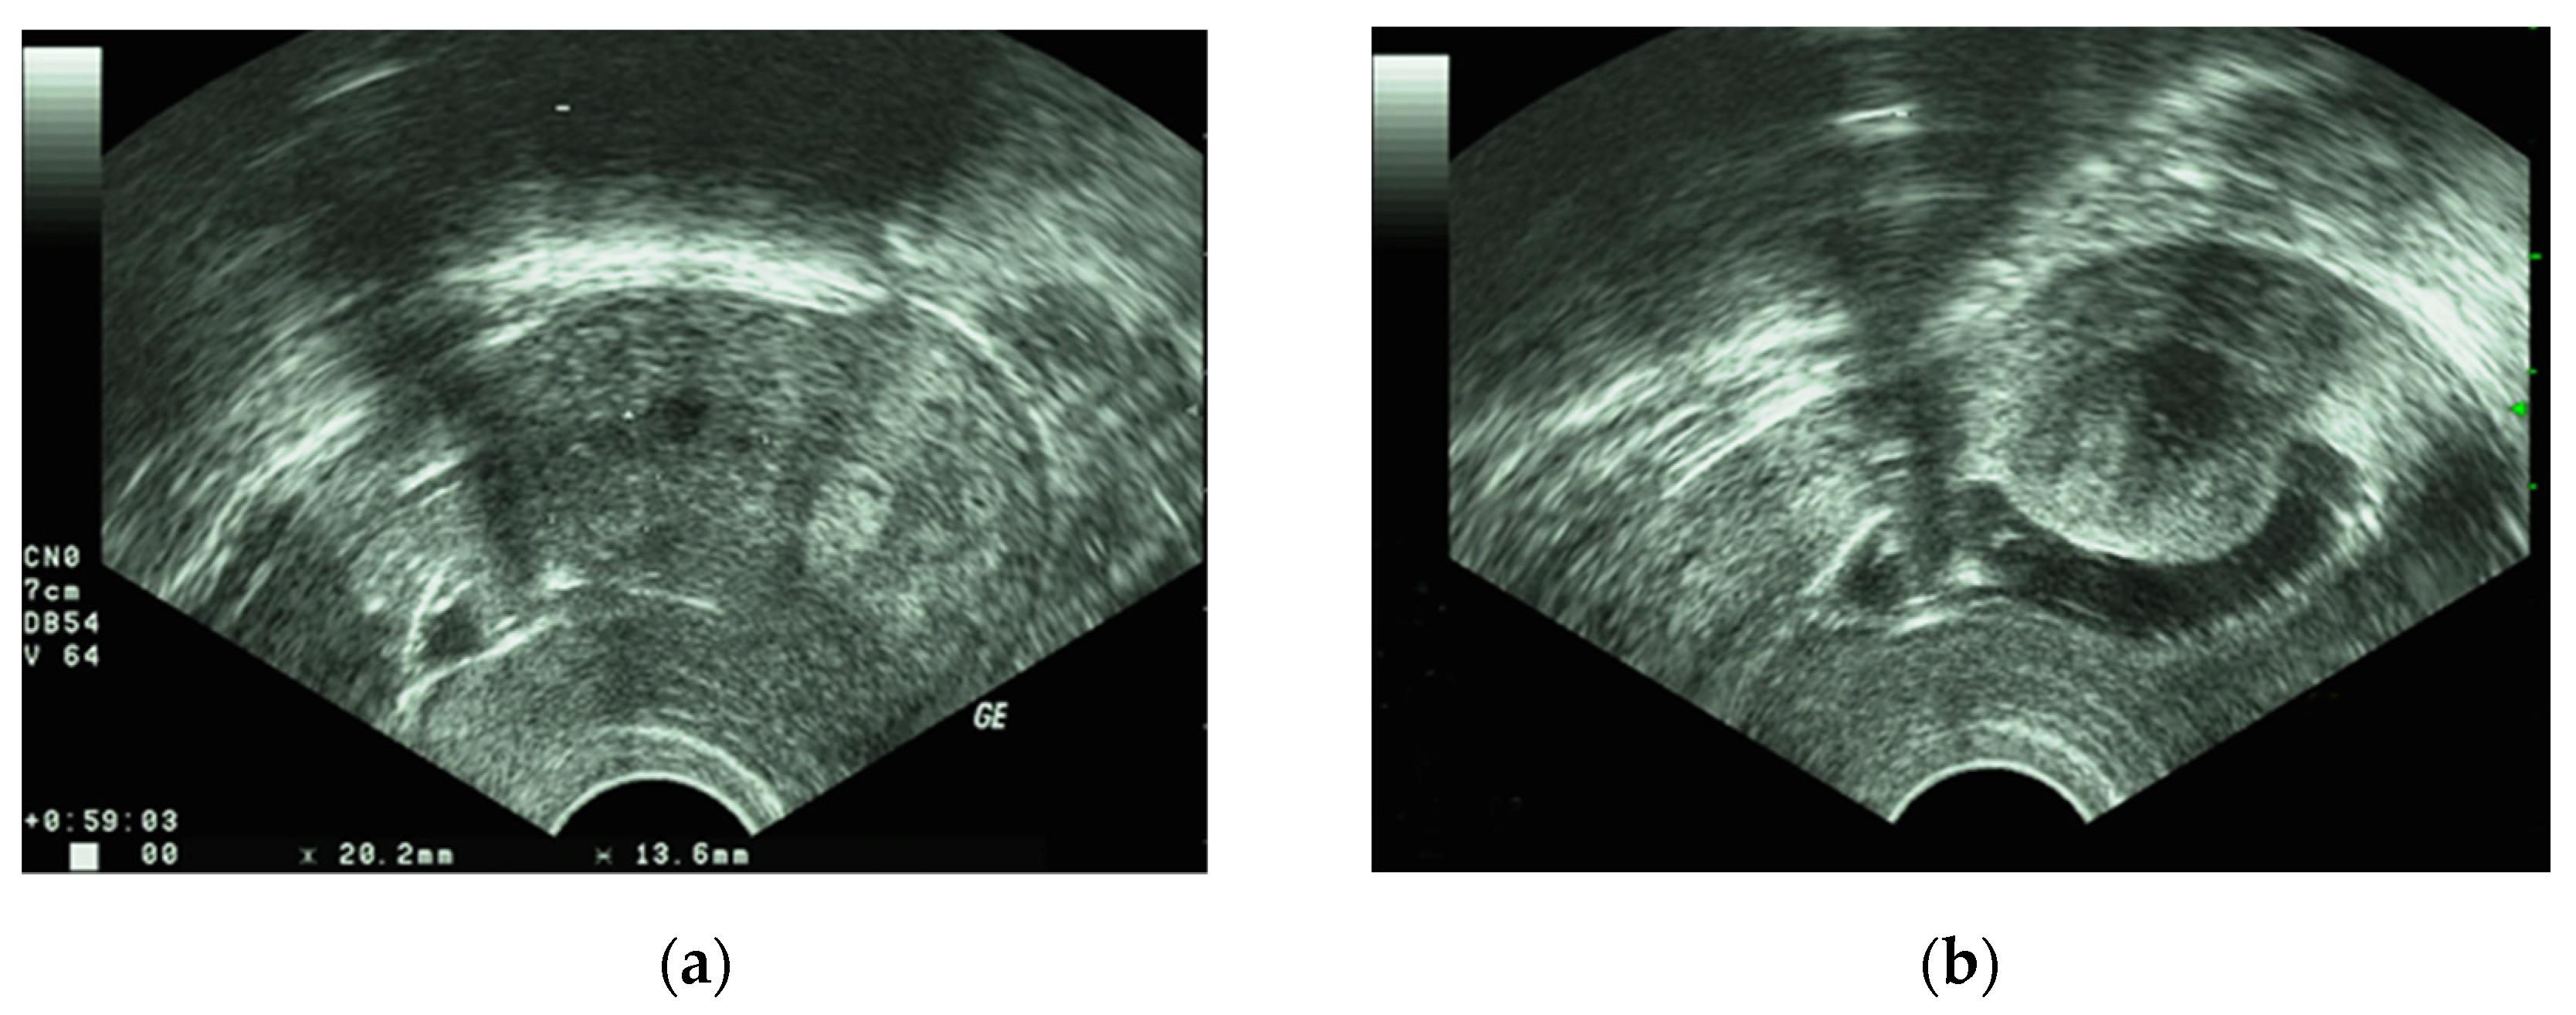

- Seshadri, S.; El-Toukhy, T.; Douiri, A.; Jayaprakasan, K.; Khalaf, Y. Diagnostic accuracy of saline infusion sonography in the evaluation of uterine cavity abnormalities prior to assisted reproductive techniques: A systematic review and meta-analyses. Hum. Reprod. Update 2015, 21, 262–274. [Google Scholar] [CrossRef] [PubMed] [Green Version]

- Wozniak, A.; Wozniak, S. Ultrasonography of uterine leiomyomas. Prz. Menopauzalny 2017, 16, 113–117. [Google Scholar] [CrossRef]